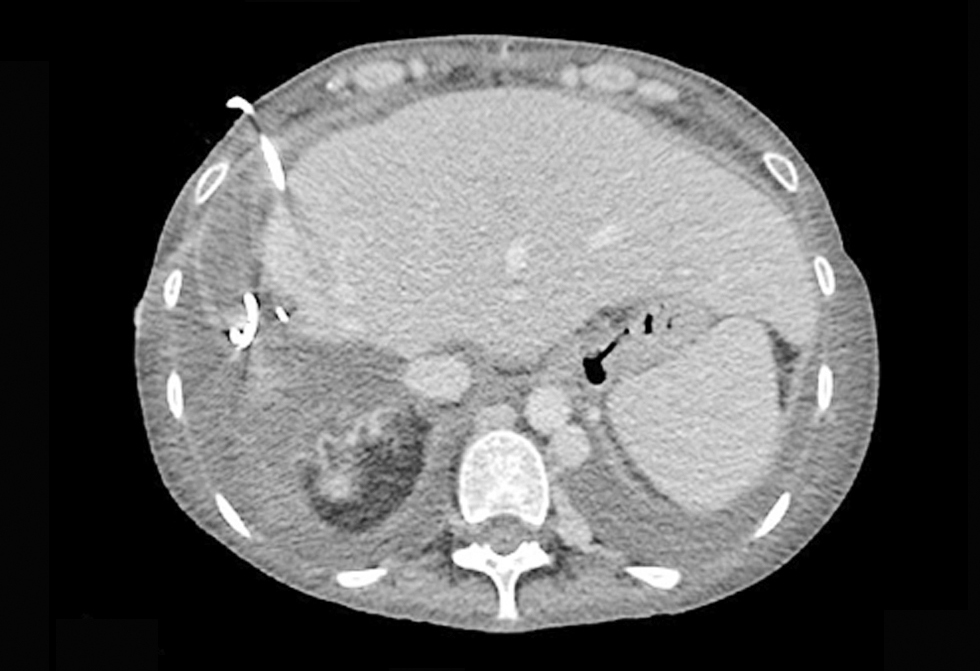

In October 2021 her CT scan revealed a cirotic liver with important portal hypertension (fig. 7).

Figure 7 - CT scan - cirrhotic liver with important portal hypertension (October 2021)